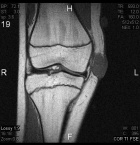

14 year old female with a tender right knee mass which has been enlarging for five months